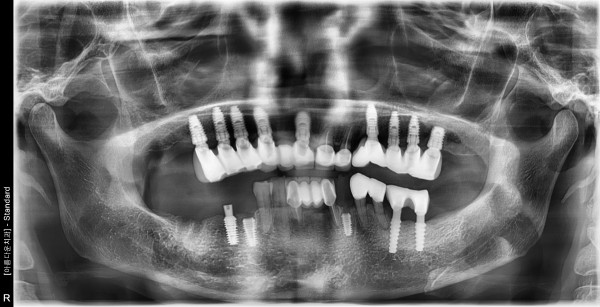

77세여자 오른쪽구치부 좌측소구치 뼈이식및 임플란트식립